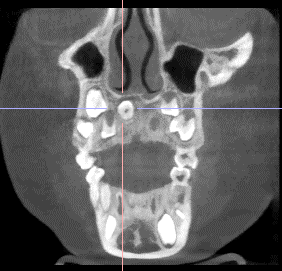

通过CBCT三维扫描,医生更清晰地看到了问题的全貌:“您看,孩子正常门牙的牙根下面,倒着长了一颗额外的牙齿。它就像个‘小捣蛋鬼’,不仅紧贴着正常牙齿的牙根,还挨着鼻腔底部。”医生指着屏幕耐心解释,“如果不及时处理,它可能会影响正常牙齿的萌出方向,甚至导致牙根发育异常。”